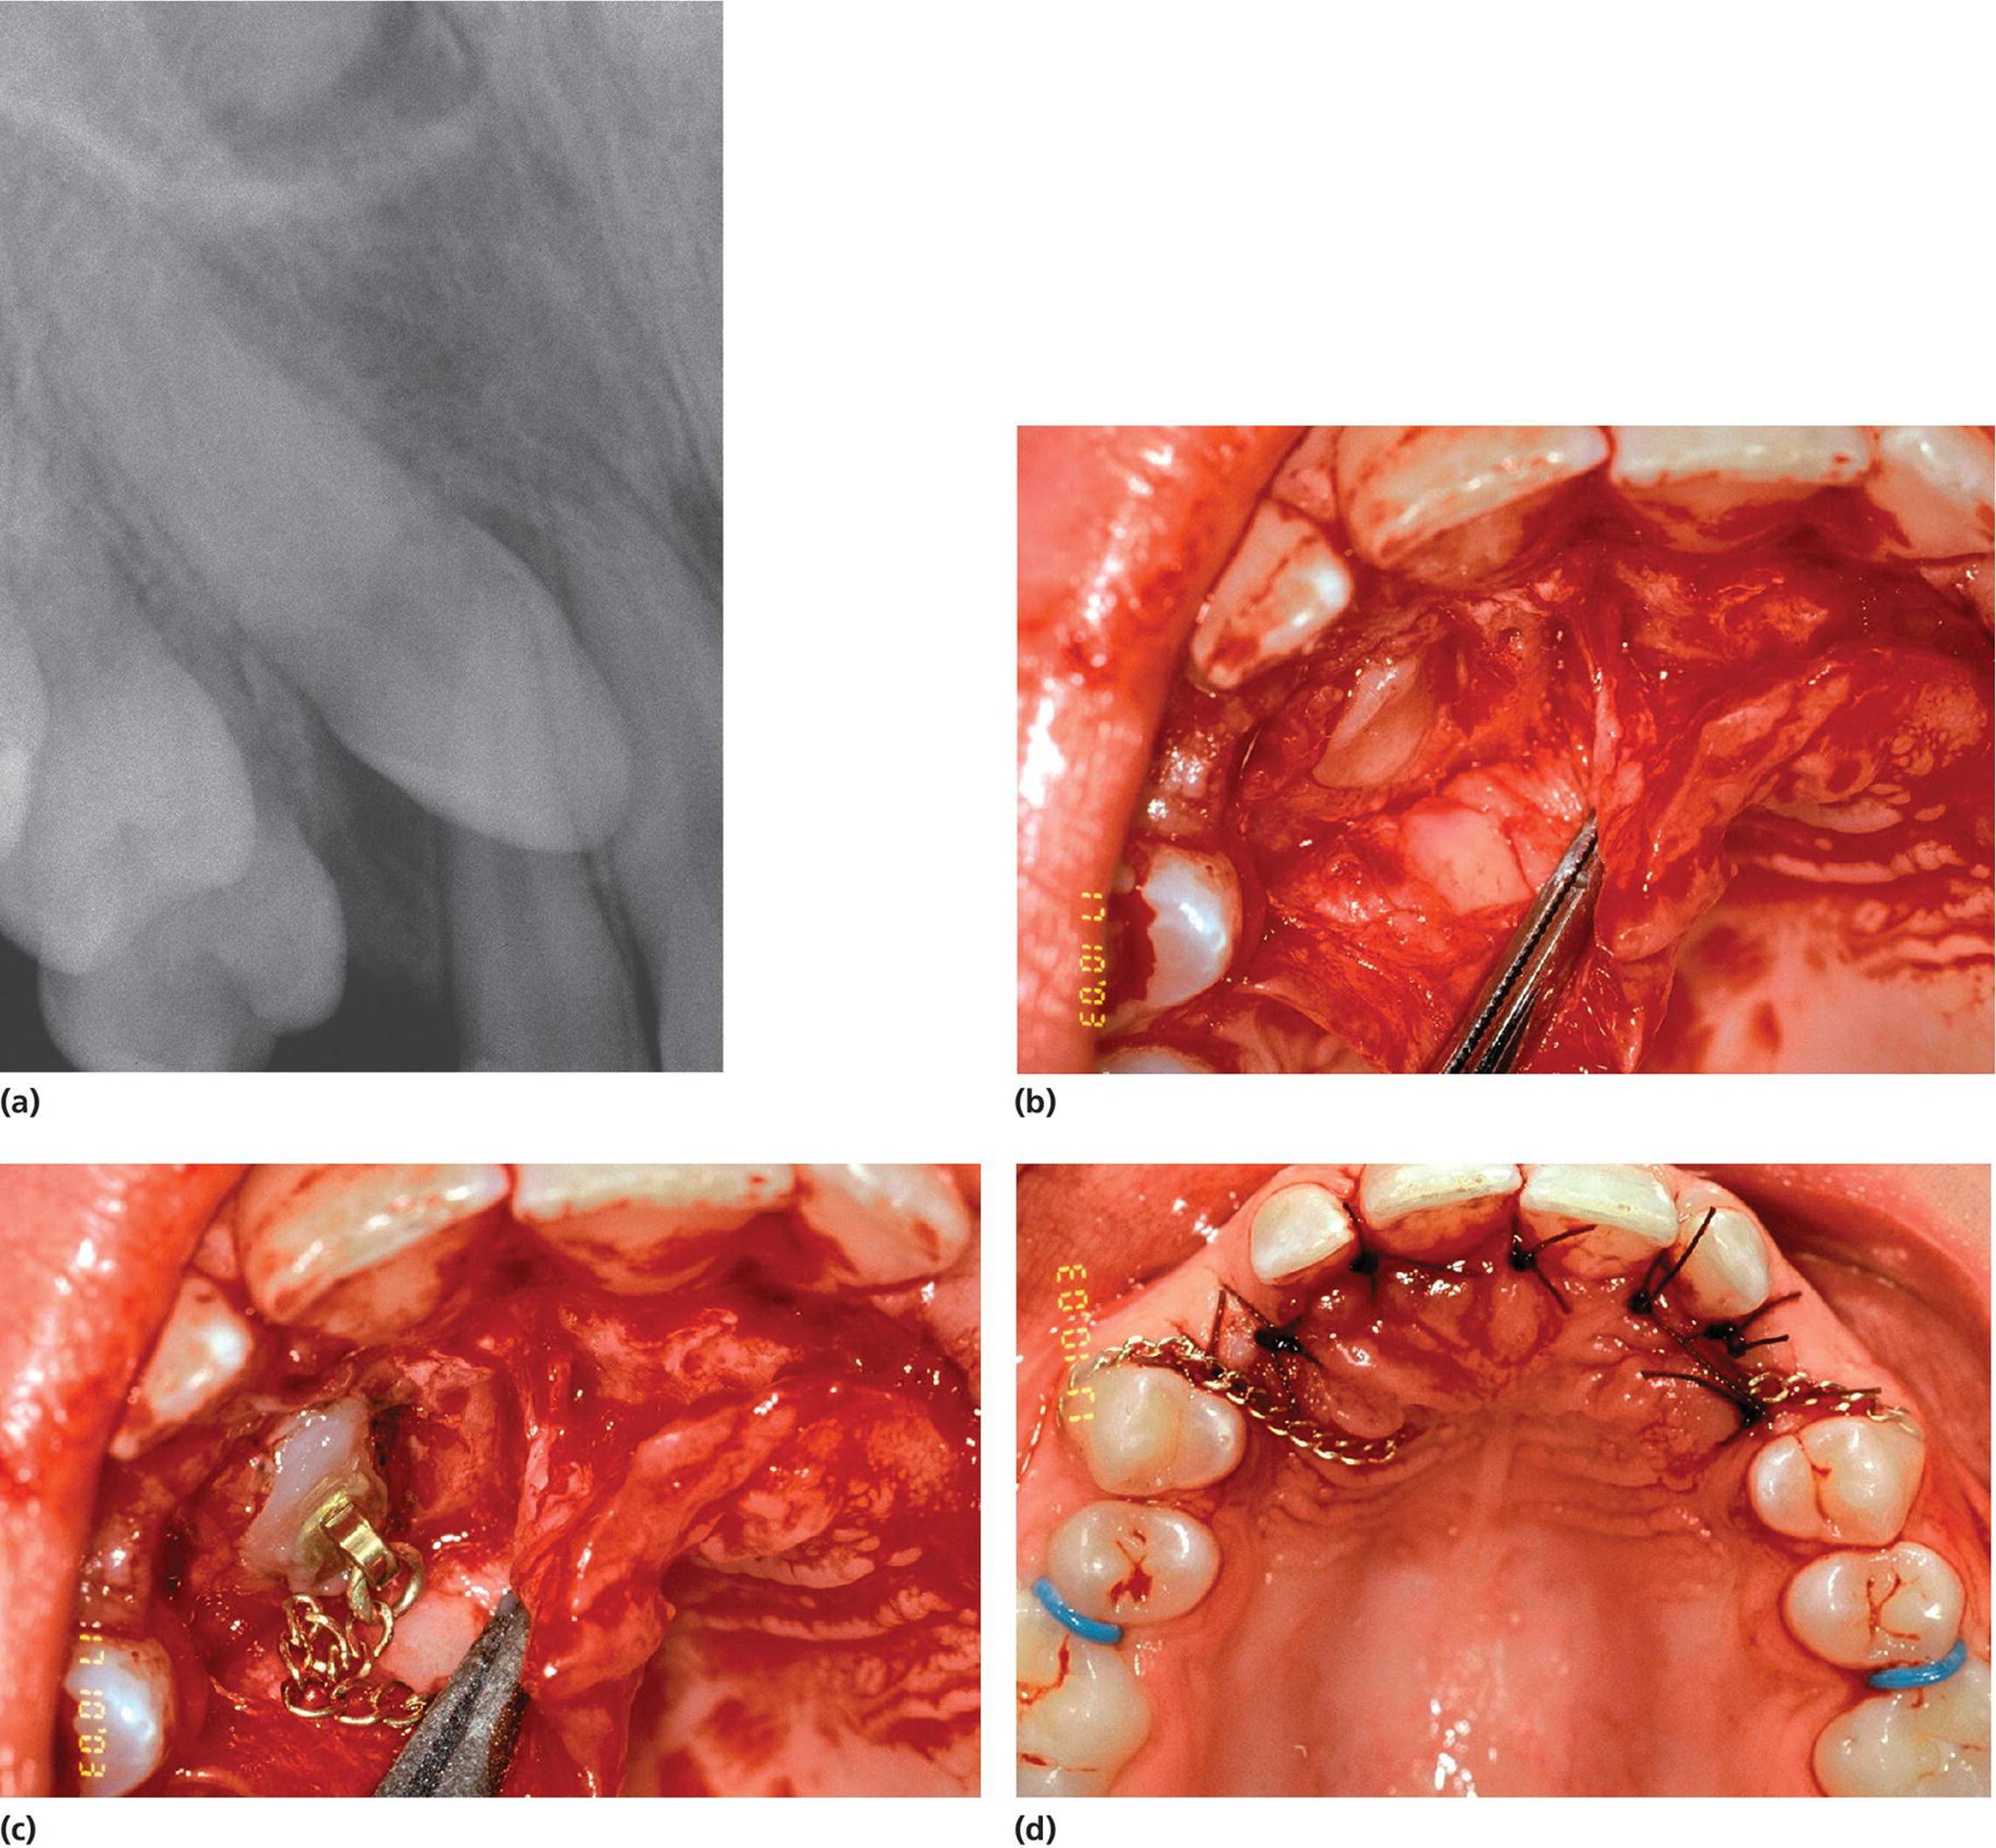

Denudation of impacted or nonerupting teeth

The surgical treatment of impacted teeth is also discussed in Chapter 5. Impacted primary teeth should generally be surgically removed. Permanent teeth with ectopic eruption position will usually be treated by surgical exposure often in combination with orthodontic treatment to guide the impacted tooth into its proper location. Such treatment is often used in cases with ectopic eruption of maxillary canines when risk for resorption of permanent incisors exists (Figure 15.27). If the eruption path for a tooth for some reason is blocked, the hindrance should be removed, and preferably when the tooth root is two‐thirds formed. In cases of early extraction of primary incisors, a delay in the eruption of the permanent incisor can occur. In such cases, a fenestration of the oral mucosa may have to be made (Figure 15.28). Impacted permanent teeth, for example mesiodens, have to be surgically removed if they interfere with eruption of surrounding teeth, cause abnormal positions of erupted teeth, or develop pathologic conditions in the region.

Figure 15.27 (a) Radiographs of upper right canine in palatinal ectopic position with risk for resorption of the permanent incisors. (b) After a palatinal muco‐periostal flap is raised and bone is removed the canine is exposed. (c) Brackets and gold chain are etched to the lingual surface of the canine. (d) The flap is sutured and the free end of the chain is temporarily fastened to a premolar. The contralateral canine was treated at the same session. The patient is now ready for the orthodontic treatment.